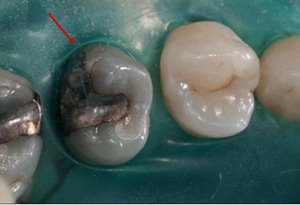

La investigación y la  experiencia clínica nos ha demostrado que la colocación de este material no es necesario, e incluso su uso puede, en ciertos casos, ser un inconveniente  para la perdurabilidad de la restauración, fundamentalmente porque merma la capacidad de adhesión de los materiales y porque su lenta disolución perjudica la estabilidad de la restauración.1,2,3(Fig.1)

Image

Fig 1. Estado de una base de hidróxido de calcio al retirar un composite antiguo.